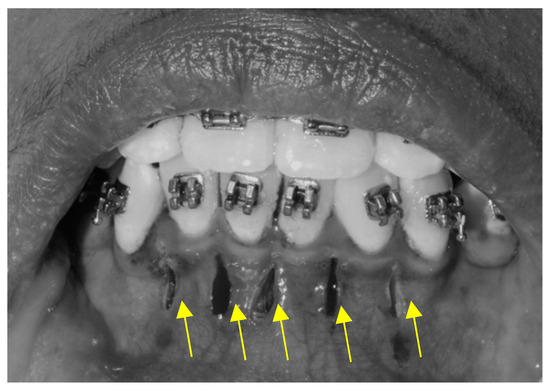

2.3.1. Piezocision Procedure (PZ)

2.3.2. Micro-Osteoperforation Procedure (MOP)